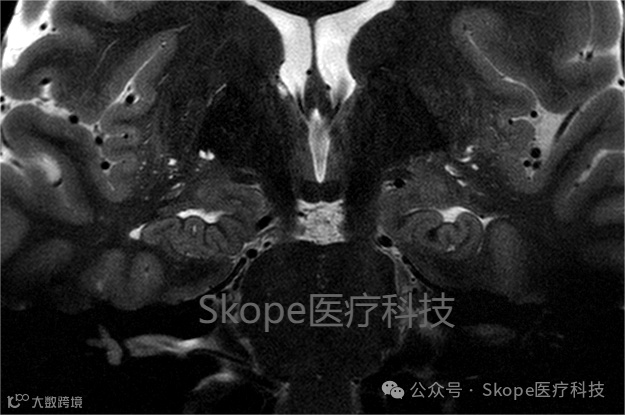

海马T2加权成像

来源:Skope

采集参数

视野:80 x 162 毫米

层厚:42 层

平面分辨率:0.2 x 0.2 毫米

层厚:1.5 毫米

PE加速因子:2

采集时间:6:12

CP模式